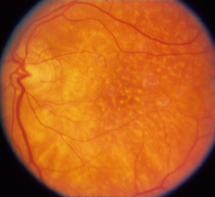

Figure 6: Three FA fundus images with symptom of drusen and corresponding generated images. (a), (b), (c) Original images. (d), (e), (f) Generated images.

4.3 Style Transferring Neural Networks

Style transferring neural network in [16] was modified to generate new disease images. This network adopts layers from ”conv1 1” to ”conv4 1” in pre-trained VGG-19 [24] network for the encoder, whose weights are provided by ImageNet-pretrained weights. What’s more, multi-level stylization strategy proposed in [16] is applied to optimize the VGG features in different layers. Input images are three CFP images and three FA images as style images shown in Fig. 2 and 5. Six CFP images with three drusen and three GA images in Fig. 3 and Fig. 4. Also, FA images are applied to generate new images in Fig. 6 and Fig. 7. For CFP images, six images are shown in Fig. 3 and in Fig. 4. In Fig. 3, generated images contain round, discrete yellow-white dots, which are the symptom of drusen. In the same way, in Fig. 4, well-demarcated areas appear on the three images. Therefore, style transferring can generate new retinal symptom images.

Furthermore, generated images from FA images are presented in Fig. 6 and Fig. 7. Results in the images are nearly identical to the original images, because original networks are applied to stylize color images. However, six generated images contain more concise features than the original ones, which helps ophthalmologists make better judgments. Therefore, this style transferring networks can fulfill edge sharpening and enhancement of contrast. No matter which kinds of images are generated, advanced features in new disease images still exist. Furthermore, analyses of image performance by EyeNet and CAMs for prediction are presented in a later section.